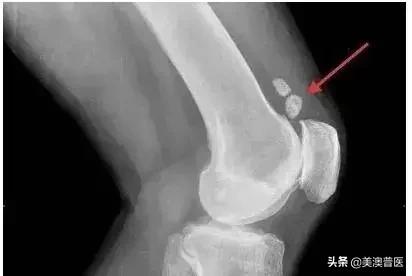

其好发的部位是膝盖,大腿,脚踝,肩膀,胳膊肘,手腕和髋部。尤其是手足,大概有80%。

但是滑膜肉瘤只是发病在关节附近,而不是关节里面,跟正常的滑膜组织也没关系,只是因为其肿瘤细胞在显微镜下看起来与原始滑膜细胞相似。

影像学检查对于确定肿瘤大小与局部累及范围非常重要,超声经常是最先进行的检查。而在任何治疗前,原发部位的CT或MRI是必须做的,用于评估局部累及范围。在确定软组织受累范围时,肢端MRI通常作为首选。